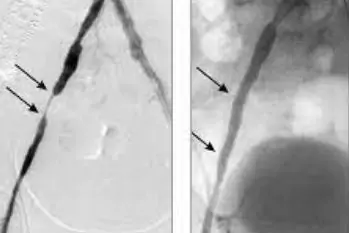

Récemment, mon travail se concerte sur une méthode innovante de la lutte contre l'ischémie, qui provoque déjà une véritable révolution dans le monde. Je pense qu'il s'agit d'une véritable avancée dans la médecine naturelle, utilisée depuis des années dans le domaine de l'angiologie.

Des recherches effectuées ont démontré que l'action des ingrédients contenus dans la formule Cariovico fait baisser presque immédiatement le "mauvais" cholestérol, donc sa fraction LDL, tout en normalisant le métabolisme de glucoses et de lipides de l'organisme. Grâce à cela, Cariovico minimise le dépôt de plaques d'athérosclérose dans les artères.

Restaurer le bon profil sucre-graisse dans le corps est extrêmement important, mais ce n'est pas tout. Cariovico a la capacité de ramollir, de desserrer et - enfin - de dissoudre progressivement les dépôts dangereux accumulés au fil des années dans les vaisseaux sanguins. Ils sont évacués du corps en toute sécurité.

La haute efficacité de la préparation Cariovico est garantie par les extraits les plus puissants d'origine naturelle qui, grâce à l'action de la synergie intensifient leurs propriétés mutuellement. Cette formule a été proclamée comme une percée dans l'angiologie naturelle. Ce produit est différent des autres méthodes non invasives - il fait baisser le mauvais cholestérol LDL, rétablit l'équilibre du profil lipidique de l'organisme, facilite le nettoyage naturel des dépôts lipidiques des vaisseaux sanguins, restaure leur élasticité et les renforce, tout en minimisant le risque d'engorgements et de gonflements.